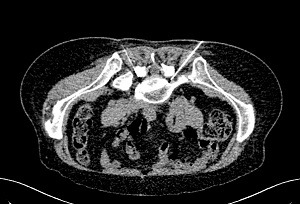

筆者轉介患者給䐉神經外科,進行一項名為 ”椎間孔選擇性神經根阻隔術",這是一個注射程序,醫生透過x光導引下把局部麻醉劑及類固醇注射在神經根上。目的是要把受影響的神經根局部麻醉,令患者的腰腳痛大大減輕。患者經注射後,腳痛大大改善,可繼續進行保守性治療,患者和家人都感到非常高興和欣惠,原來可在保守治療與手術治療之間,還可以選擇以"最低入侵性冶療”的辨法。

正進行左邊腰椎4,5節椎間孔選擇性神根阻隔術

正進行左邊腰椎4,5節椎間孔選擇性神根阻隔術